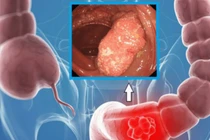

Ca mổ nội soi thành công cho bệnh nhân 95 tuổi mắc ung thư đại tràng tại Bệnh viện K thể hiện khả năng điều trị hiệu quả cho người cao tuổi.

Ê-kíp đã quyết định thực hiện phẫu thuật nội soi cắt khối u nhầy ruột thừa kích thước lớn (15x5 cm) kèm toàn bộ manh tràng.